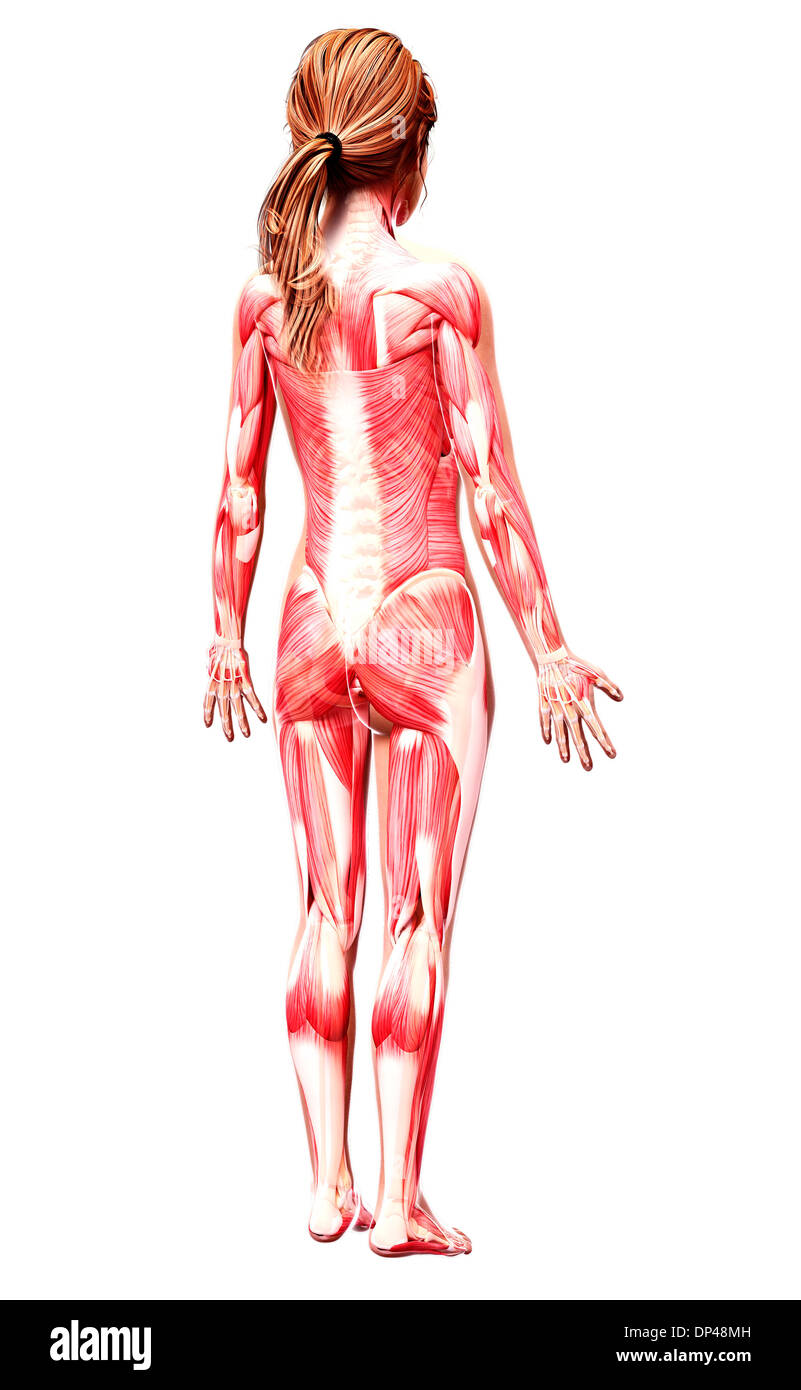

Female anatomy, artwork Banque D'Imageshttps://www.alamyimages.fr/image-license-details/?v=1https://www.alamyimages.fr/female-anatomy-artwork-image65233044.html

Female anatomy, artwork Banque D'Imageshttps://www.alamyimages.fr/image-license-details/?v=1https://www.alamyimages.fr/female-anatomy-artwork-image65233044.htmlRFDP3HBG–Female anatomy, artwork